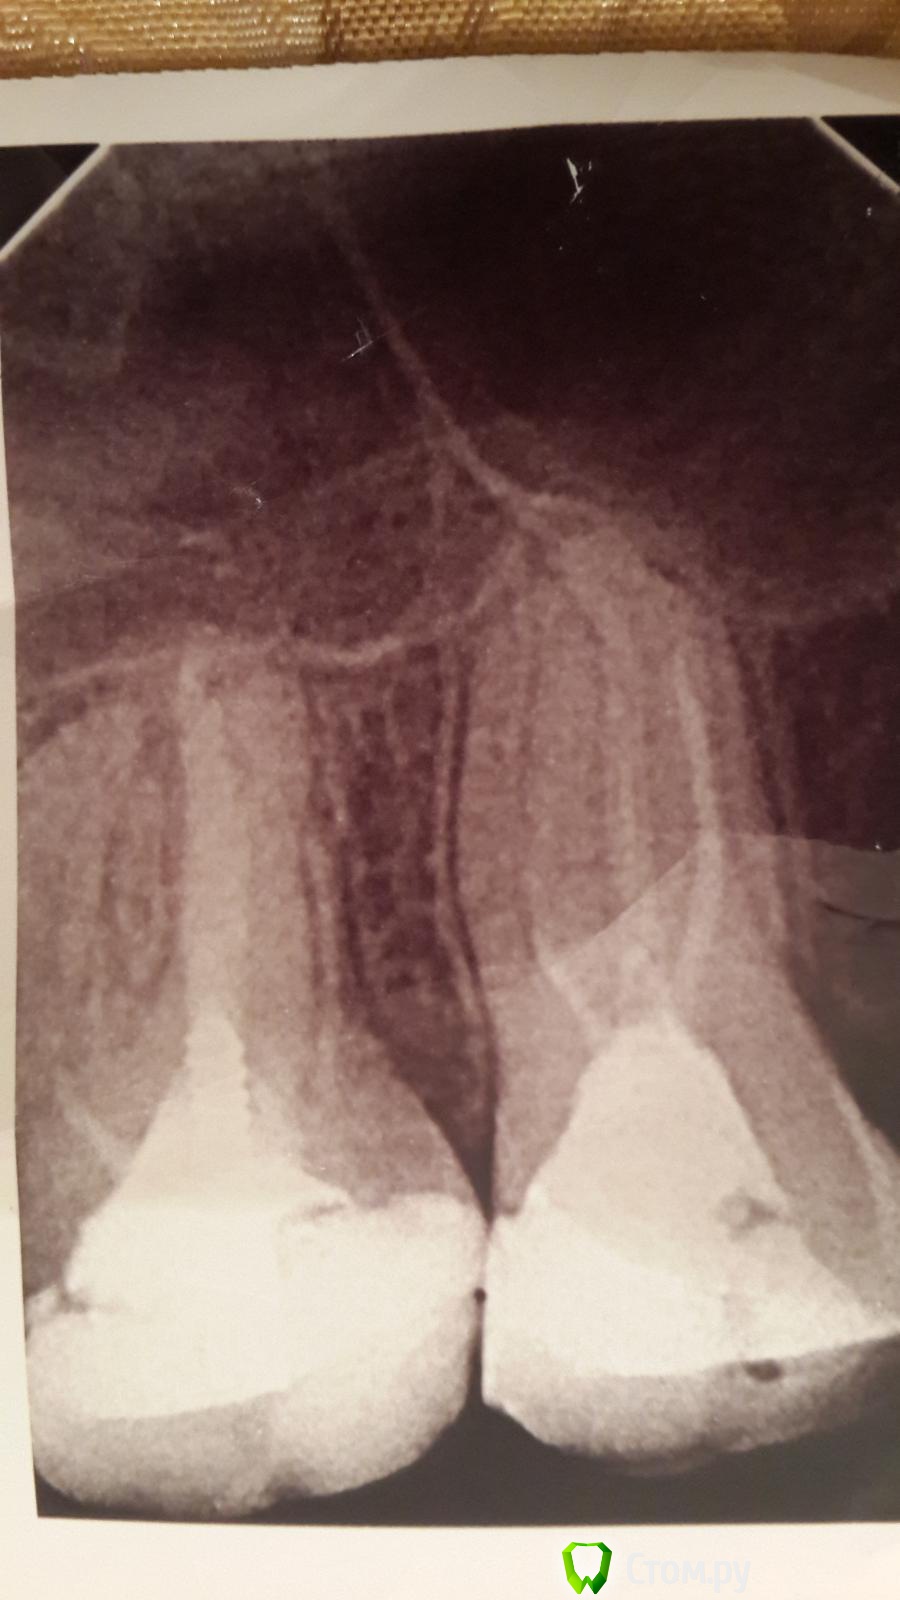

Ниона Опубликовано 11 марта, 2014 Поделиться Опубликовано 11 марта, 2014 Сегодня обратилась пациентка, 27 лет. В течении 2х недель беспокоят боли от горячего, холодного и от сладкого в зубах на верхней челюсти слева. В основном в области 2.6 и 2.7. На этой стороне от 2.3 до 2.7 все зубы депульпированы. Зондирование, перкуссия везде отрицательны. Слизистая без патологических особенностей. Карманов тоже не обнаружила. На воздух и воду реагируют 6й и 7й, боль иррадиирует по скуле в висок. Снизу все зубки проверила - реакции никакой. Единственное, каналы во всех 5 зубах запломбированы посредственно, какой-то пастой и не до верхушек. 2.6 и 2.7 были лечены год назад, по снимку в каналах тоже безобразие. Пациентке объяснила про остаточный пульпит, но сама я в это слабо верю. Будем перепломбировывать каналы. Я чуть больше года работаю, в первый раз такой случай. Может кто-нибудь сможет объяснить мне от чего может быть столь многогранная реакция "мертвых" зубов? Ссылка на комментарий

Каплан Опубликовано 11 марта, 2014 Поделиться Опубликовано 11 марта, 2014 в 6 очень похоже по снимку что 2 канала медиальных. очень внимательно... Ссылка на комментарий

Ниона Опубликовано 11 марта, 2014 Автор Поделиться Опубликовано 11 марта, 2014 в 6 очень похоже по снимку что 2 канала медиальных. очень внимательно... То есть, реагирует 4й канал. Правда уже год прошел. Может из-за нарушения целостности пломбы есть скол на контакте). Спасибо! начну с 6го и поищу канал Ссылка на комментарий